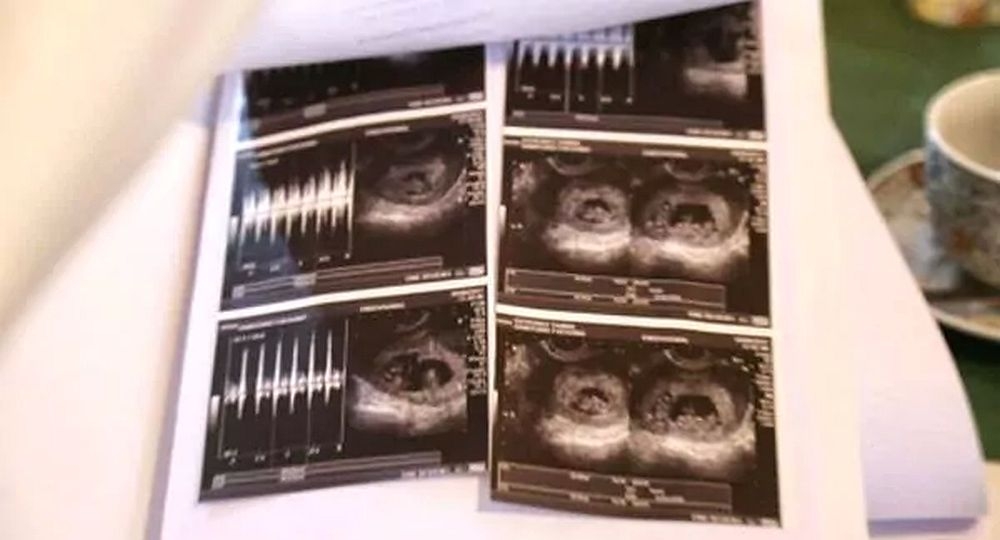

Se agrandará la familia para Yanina y Matías, una pareja de fueguinos que serán padres por primera vez. Pero su situación es bastante atípica, porque tendrán cuatro hijos en la misma fecha, precisamente, mellizos y gemelos.

"El médico no sabía cómo contarnos la noticia. Veíamos algo raro en la ecografía pero no entendíamos", dijo la mujer tras los primeros resultados. Y agregó a los medios: “Yo veía tres bolsitas, pero como es la primera vez que transitamos esto, no sabíamos de qué se trataba, por eso nos quedamos callados".

Pero la sorpresa fue mayor cuando el médico confirmó que eran cuatro.  “En cada punta están los mellizos y en el medio los gemelos", relató la futura madre.